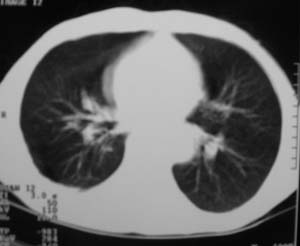

男,54岁,无任何不是感.体检发现右肺部阴影.现行ct进一步确诊.

右侧胸廓塌陷,肋间隙变窄,肋骨增生变粗,脏壁层胸膜肥厚、钙化。符合陈旧性结核性脓胸改变

右侧包裹性积液伴胸膜钙化.

右侧包裹性积液并胸膜钙化,性质还是结合穿刺细胞学检查的好,结核性、化脓性均会有钙化。

右侧胸膜肥厚、粘连、钙化。

周围都钙化了应该不是积液了吧,这样都没有不适感,病史不详